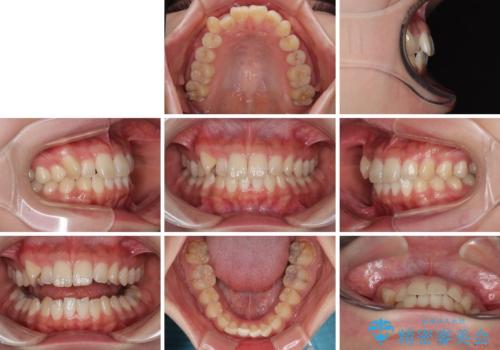

- 上下前歯のデコボコを気にして来院された患者様です。

ワイヤー矯正でもマウスピース矯正でも可能でしたが、短期間で、自身の手を煩わせることなく治療を行いたいとのことで、ワイヤー装置にて矯正治療を行うこととしました。

僅か8ヶ月という短期間で、綺麗な歯列に仕上がりました。